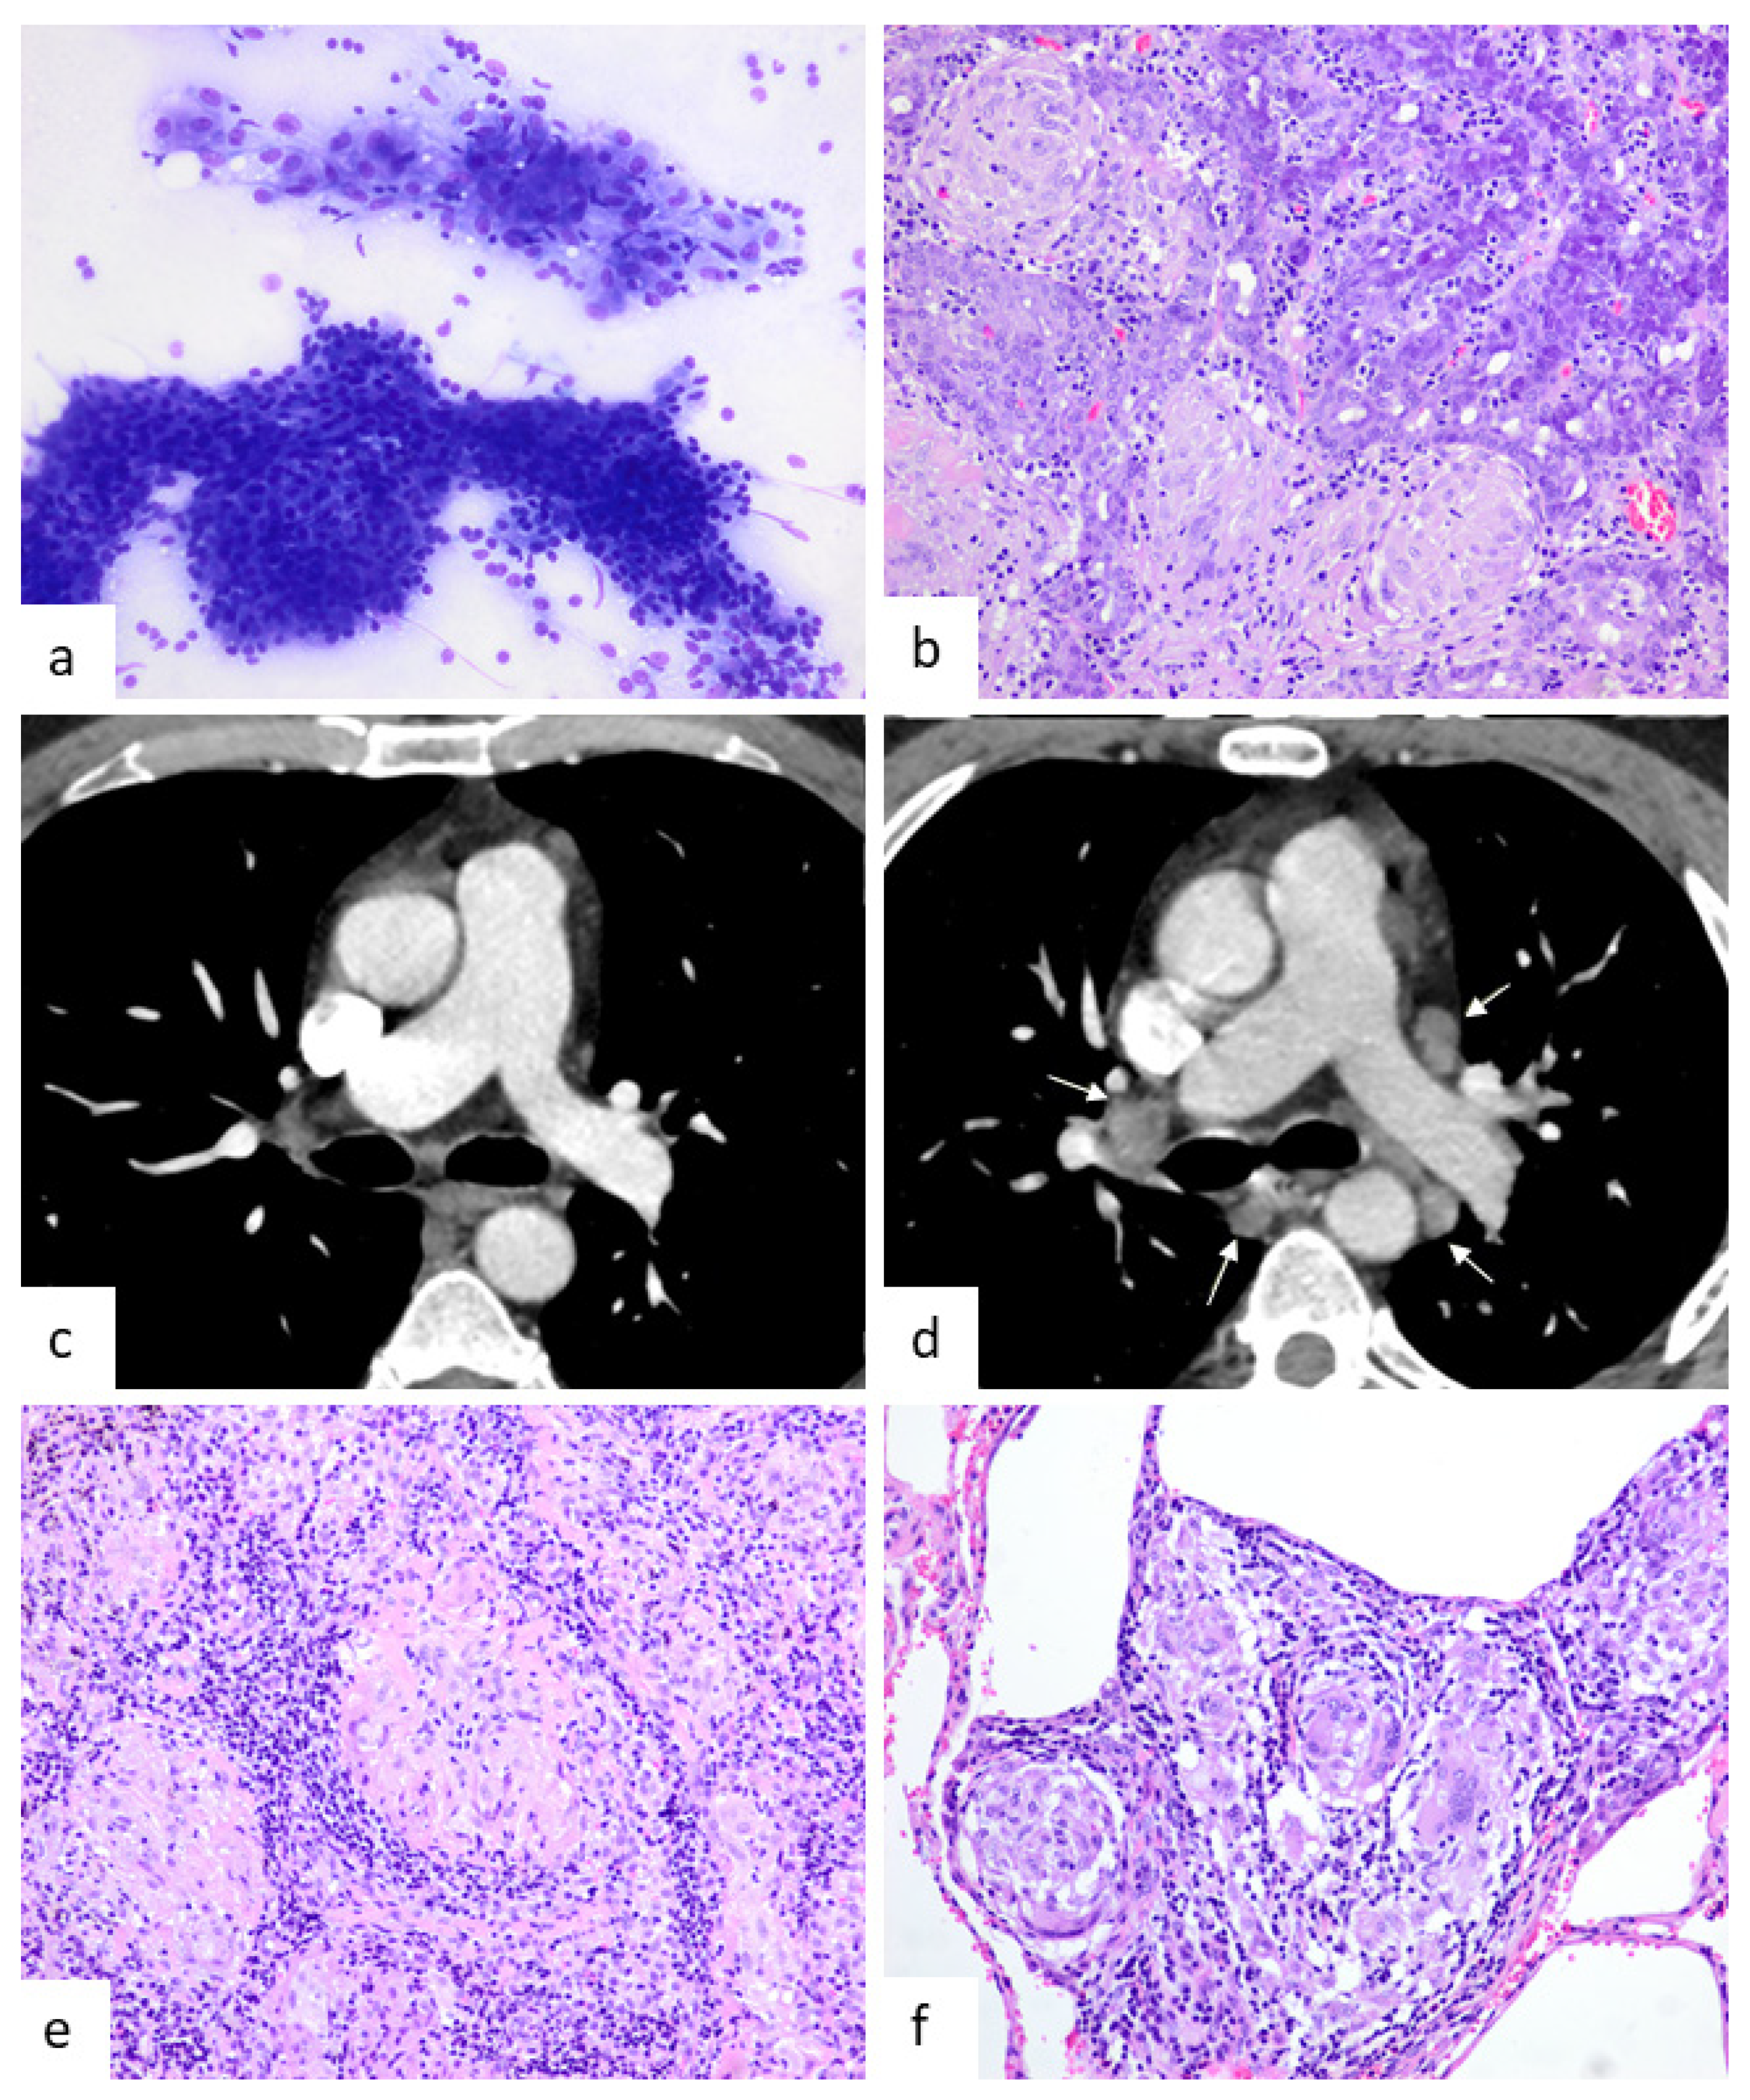

Tumor-Associated Granulomas Preceding a Diagnosis of Thoracic Sarcoidosis: A Retrospective, Single-Center Cohort Study

3. Results